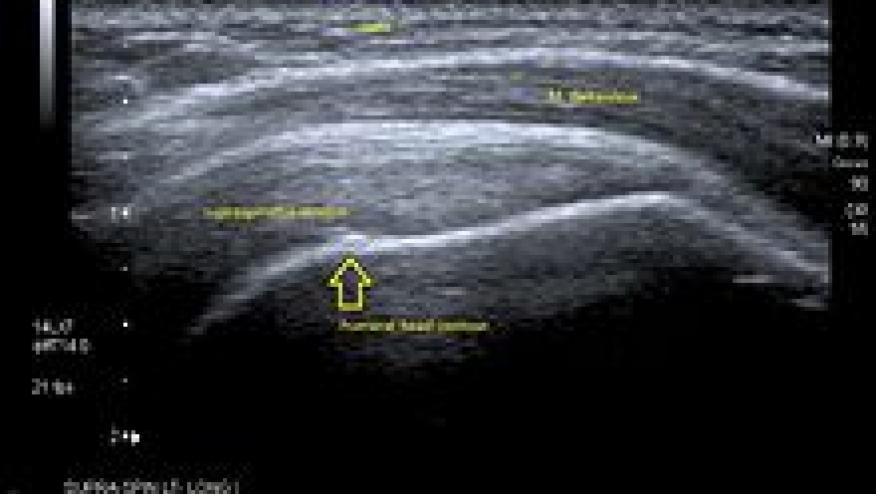

The recent inclusion of ultrasound in the classification criteria of various rheumatic diseases, such as polymyalgia rheumatica and gout, implies this imaging technique is not onlyuseful as a valued diagnostic tool for individual cases, but also on a larger scale, it will improve doctors' ability to classify diseases. Source article:http://www.medultrason.ro/assets/Magazines/Medultrason-2015-vol17-no1/Ar... credit: "Longitudinal US supraspinatus" by RSatUSZ - PACS UniversitätsSpitalZürich. Licensed under GFDL via Wikimedia Commons]